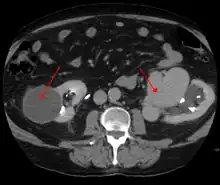

AVMs can occur in various parts of the body:

- brain (cerebral AV malformation)

- spleen[13]

- lung[14][15]

- kidney[16]

- spinal cord[17]

- liver[18]

- intercostal space[19]

- iris[20]

- spermatic cord[21]

- extremities – arm, shoulder, etc.